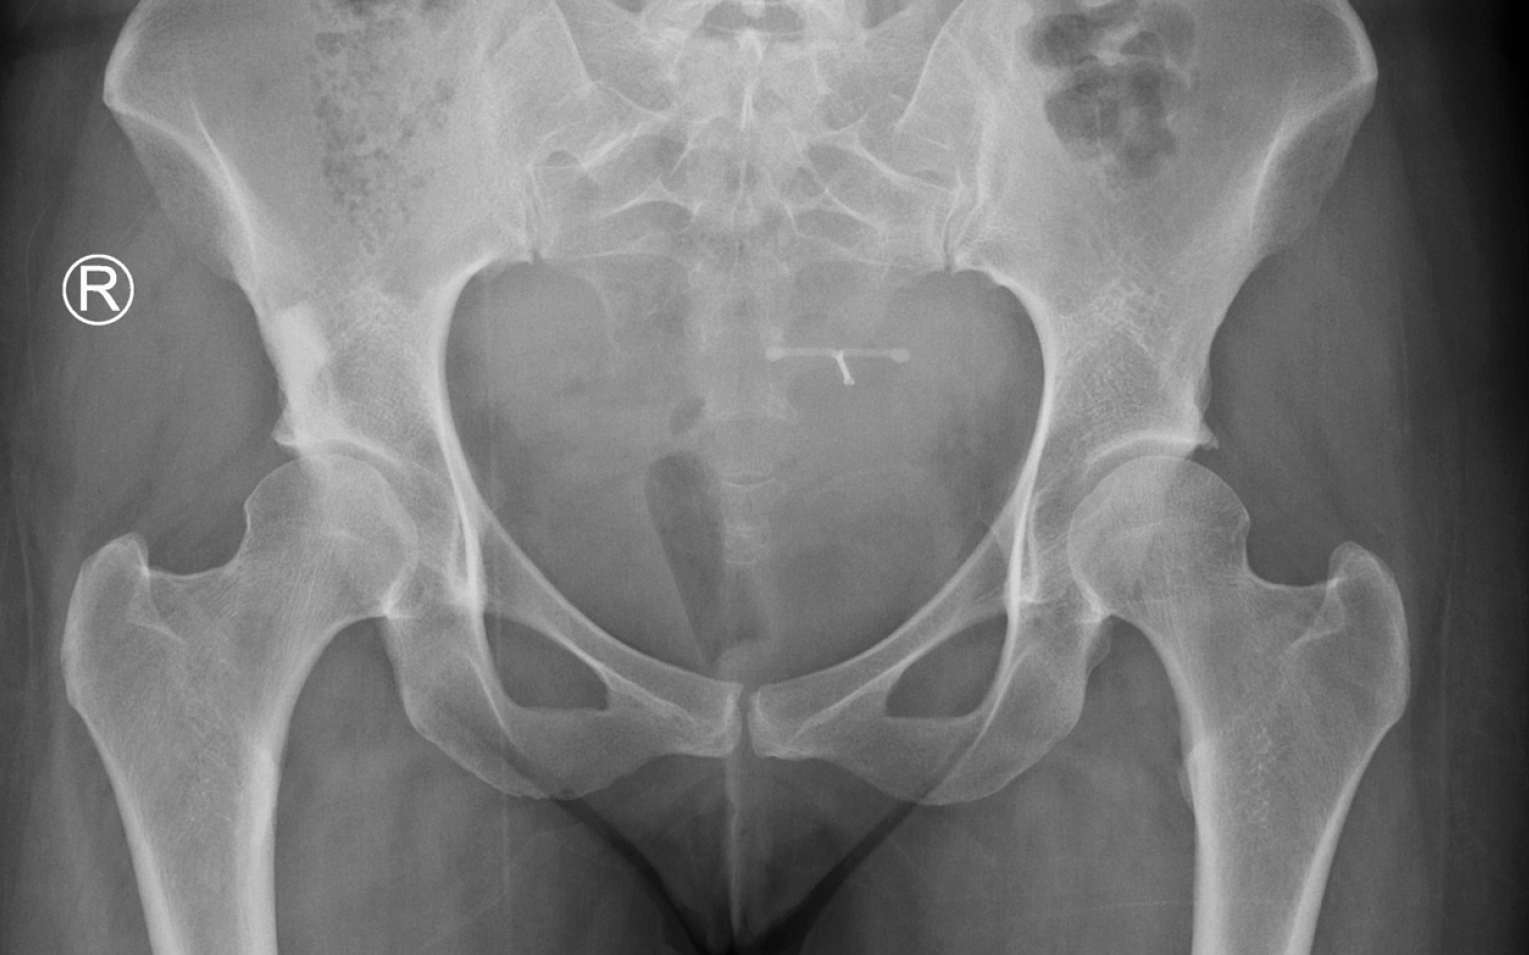

Types of hip fractures?

A hip fracture is a break in the upper portion of the femur (thigh bone), near the hip joint. These injuries most commonly occur in older adults, particularly those with osteoporosis or reduced bone density, but they can also result from high-impact trauma in younger patients, such as a car accident or significant fall.

Hip fractures are typically categorised based on the location and pattern of the break in the upper femur (thigh bone). Understanding the type of fracture helps guide the choice of surgical treatment and expected recovery pathway:

2. Intertrochanteric fractures

Located between the greater and lesser trochanters, these fractures occur just outside the hip joint capsule.